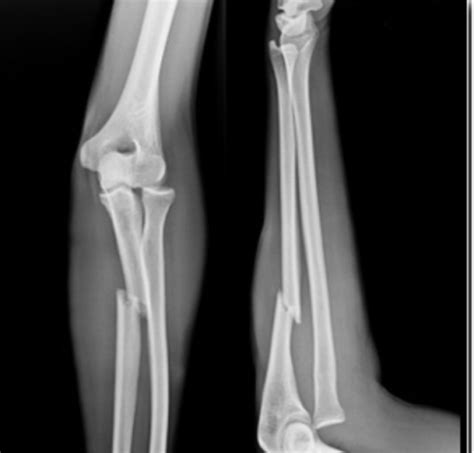

但有时候价格高并不一定看得更清楚。就拿骨折来说,X线就比磁共振要看得清楚的多,选择何种检查还是要依据病人的具体情况而定!看看下面这个X线片,是不是瞎子都可以看出来是骨折了!

腰椎间盘突出针灸有副作用吗,腰椎间盘突出针灸越来越严重